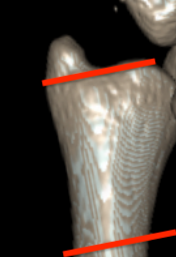

Classification ulna styloid fractures

| Type 1: Tip | Type 2: Base | Type 3: Proximal to styloid |